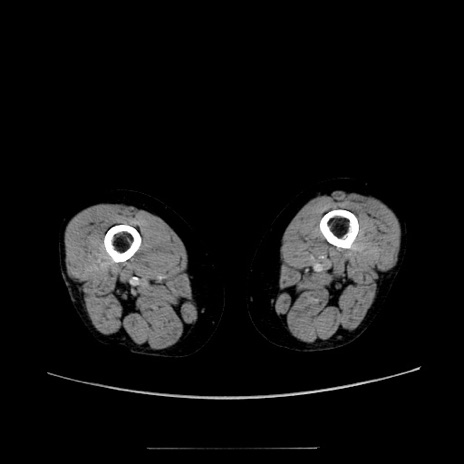

症例5(横断像)

【症例】70歳代女性

【主訴】お腹が張る

【現病歴】1週間くらい前から腹部膨満の自覚あり。昨日夜から増悪したため、本日救急外来受診。

【身体所見】意識清明、BT 36.5℃、BP 165/106mmHg、HR 80bpm、SpO2 98%、腹部:膨満、軟、自発痛・圧痛なし、触診にて不快感あり、腸蠕動音:減弱

【データ】WBC 12600、CRP 1.04